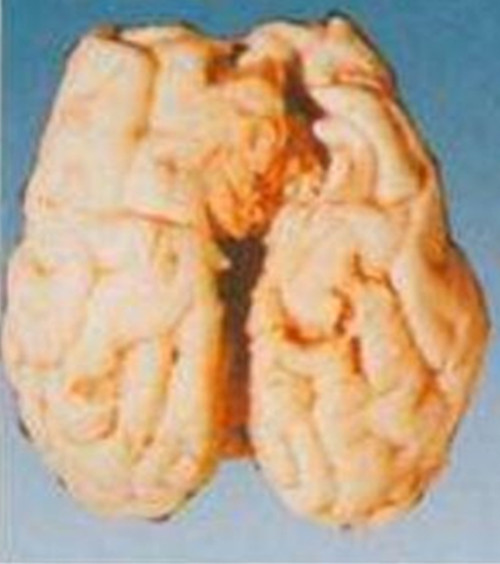

腦膜炎細菌性腦部

腦膜炎細菌性